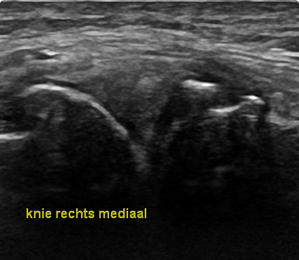

Orthopedische echografie, een blessure nader bekeken .........